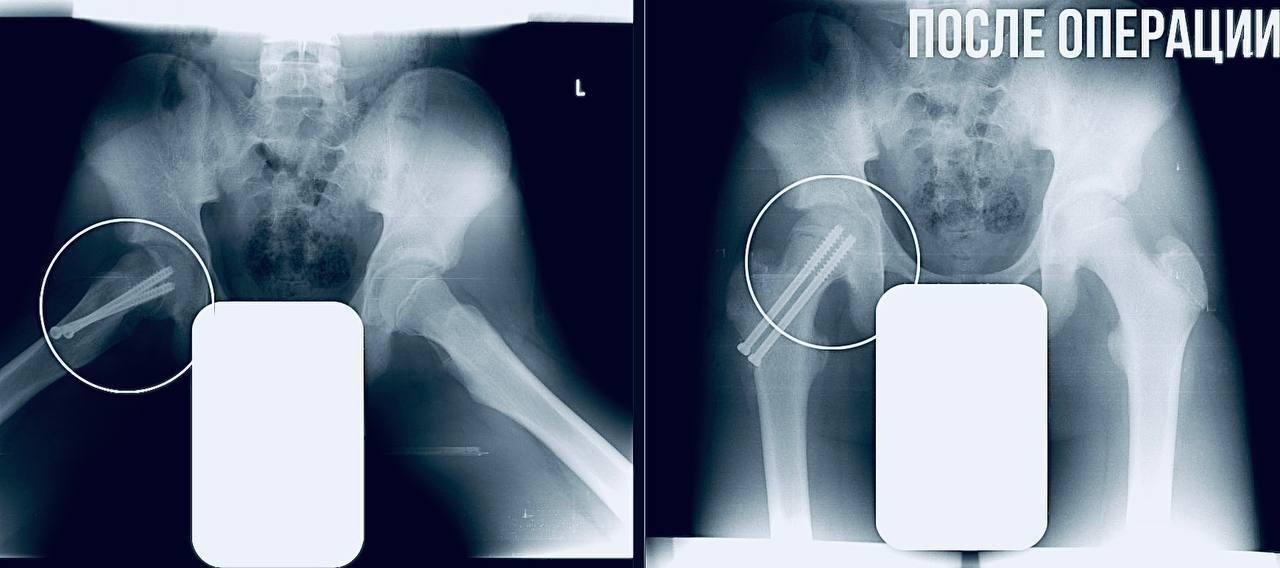

Врачи срочно провели фиксацию сустава, чтобы остановить смещение и предотвратить ранний артроз. Подросток уже идет на поправку и скоро начнёт реабилитацию.